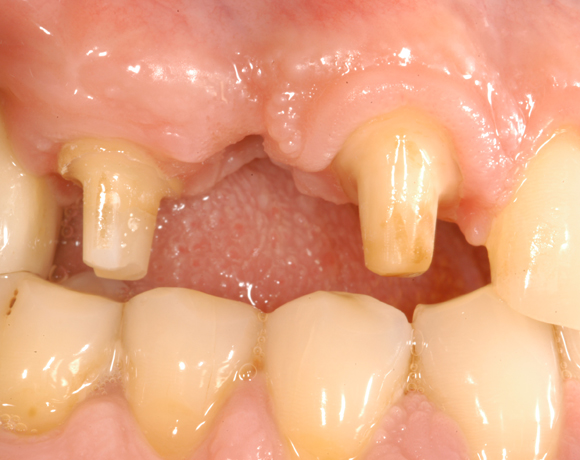

Der vorliegende Patientenfall war noch mit einem Prototypen eines vollkeramischen Aufbaus versorgt worden. Deutlich sichtbar der dunkle Rand an der VMK – Krone der metallkeramischen Versorgung. Die dunkle Verfärbung der Gingiva ist durch ein Amalgamtätoo bedingt.